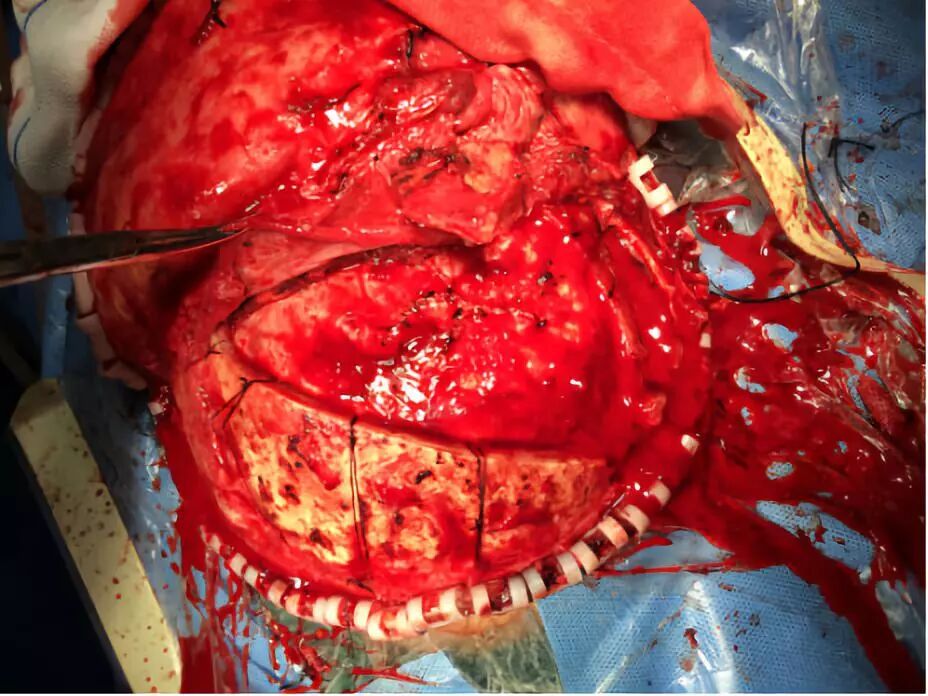

手术采用冠状切口,右侧额骨颧突部关键孔钻孔一个,左侧眉弓上方钻孔一个,离骨折边缘2-3厘米处铣刀铣成骨瓣,取下碎骨片,右侧眼眶大骨片未取下。硬膜多处裂开,清除硬膜外及少量硬膜下出血,清除少量挫裂伤脑组织,脑组织张力不高,缝合硬膜。左侧额窦予以骨蜡封闭,清除额底鼻骨碎骨片后,与鼻窦相通,复位右侧眶壁骨折。取颞肌修补覆盖颅底,封闭颅内与鼻腔眼眶之交通,再游离额部骨膜,反折覆盖颅底并固定。骨瓣及游离较大块碎骨片双氧水浸泡,依据形状复位碎骨片,缝线及胶水固定,复位骨瓣并钛钉固定。

带蒂骨膜反折覆盖颅底,加固修补

复位骨瓣